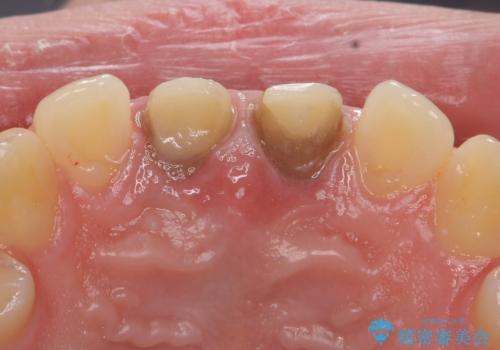

前歯の変色 神経のない歯の再治療

- 前歯の変色を気にして来院。

過去に神経の治療を行ったとのことでした。

特に右上の前歯の膿は大きくなって歯ぐきから排膿している状態でした。(フィステルといいます)

二本とも神経の治療のやり直し(再治療)を行ってからセラミックを入れています。